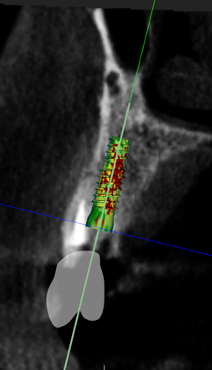

(11.) Implant position at site No. 21 optimized on the virtual plan.

Figure 11

A healthy 60-year-old female presented for an emergency evaluation because she was experiencing pain associated with tooth No. 20. It was mobile, malposed, and given a diagnosis of irreversible pulpitis. In addition, teeth Nos. 19 and 21 had been missing for more than 5 years. After the evaluation, a discussion revealed that the patient desired implant reconstruction of the lower left quadrant. During this initial visit, a CBCT scan was obtained, and the virtual restoration-driven implant planning was completed, confirming that extraction of tooth No. 20 with robot-assisted immediate implant placement at the sites of teeth Nos. 19 and 21 was a viable option (Figure 9 through Figure 13). Splint placement, CBCT capture of the fiducial array, calibration, and landmark confirmation were completed as described in the first case report. Following the administration of intravenous sedation and local anesthesia, tooth No. 20 was atraumatically extracted. Flap access was obtained from the site of tooth No. 18 to the site of tooth No. 22, and robot-assisted surgical implant placement was completed at the sites of teeth Nos. 19 and 21. Intraoperatively, guide pins were placed to evaluate the position of the proposed osteotomies, and it was determined that both implants should be tilted buccally by 0.4 mm. The necessary changes were made in the software application, and the new implant placement plan was immediately ready for robotic implementation. The implants were robotically delivered to their planned positions at the sites of teeth Nos. 19 and 21 and torqued to initial stability at 50 Ncm and 45 Ncm, respectively (Figure 14 and Figure 15). Healing abutments were placed, and the tissue was closed primarily. In this case, robotic assistance facilitated the performance of surgery on the same day that the patient initially presented and permitted intraoperative modifications to be made.